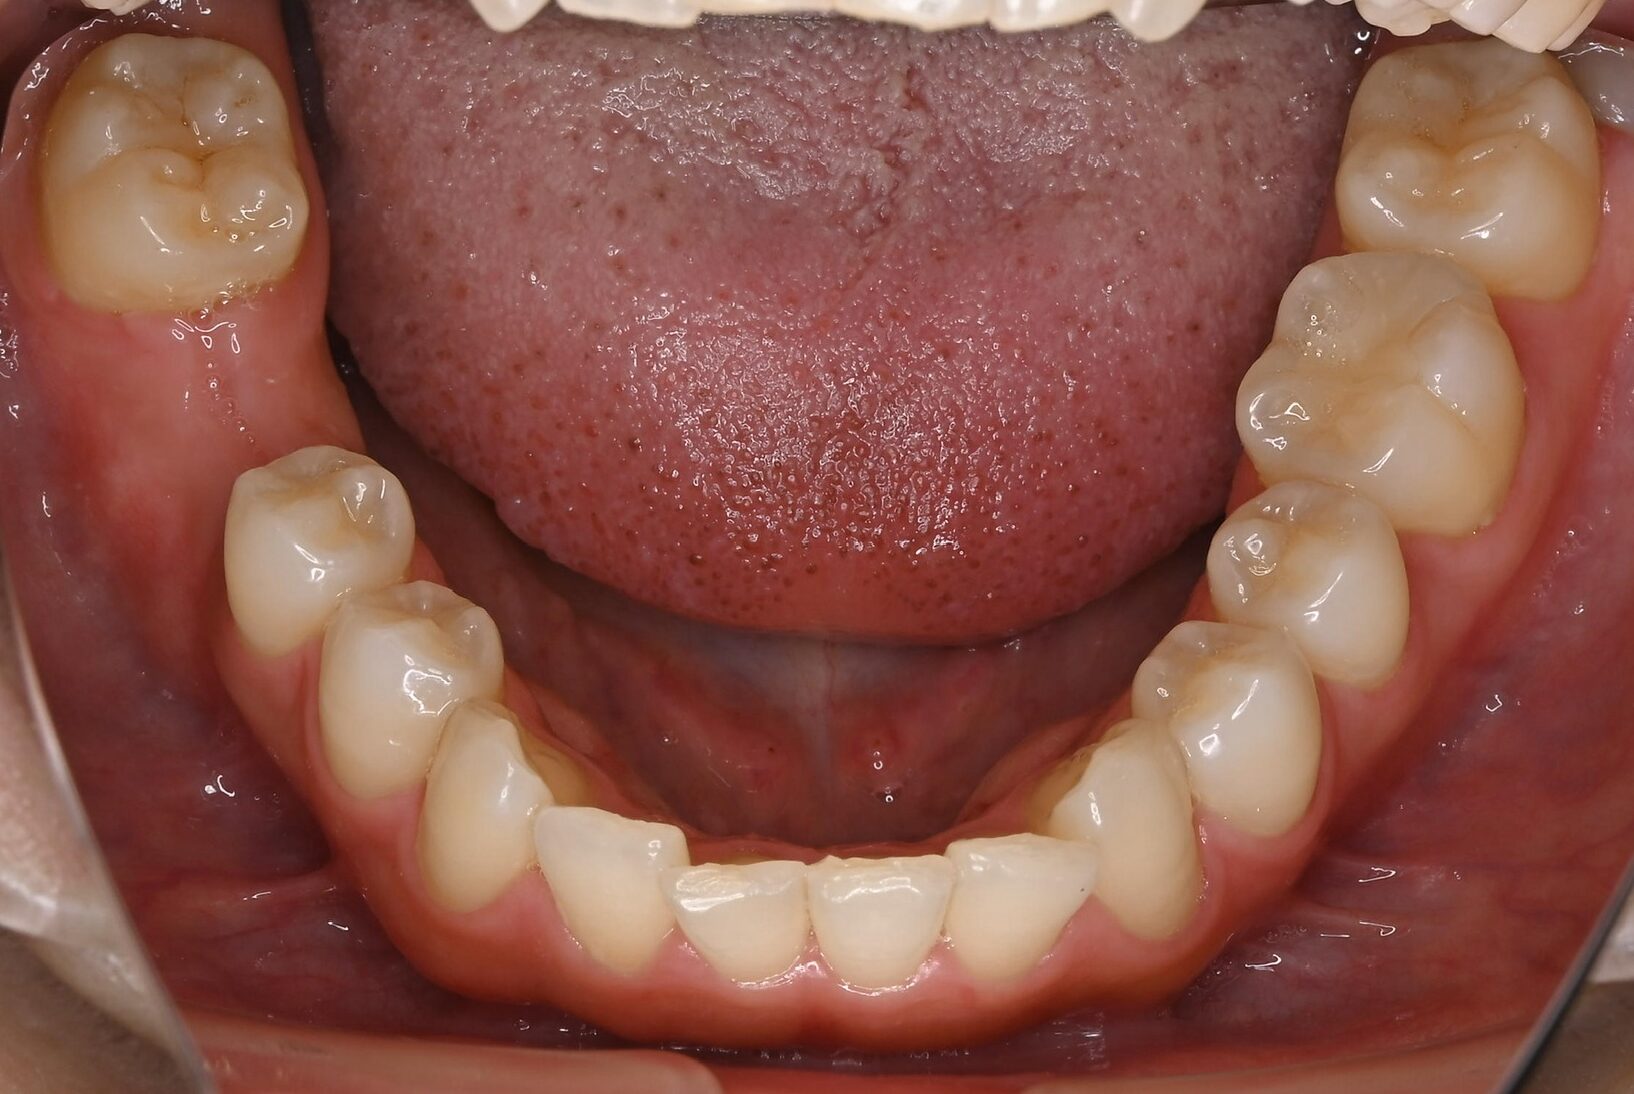

右下奥歯のインプラント症例

Before

• 右下6番欠損です。

• インプラントを埋入するのと同時にヒーリングキャップを取り付けました。

After

治療内容

右下の奥歯を根の先の膿が原因で抜歯された患者様です。

ブリッジ治療では両隣の歯を大きく削らないといけない為、インプラント治療を希望されました。

骨の治り方が歪で、頬側の骨が大きく足りないため骨造成を行い、インプラントを埋入した日にヒーリングキャップを装着し、インプラントが骨と結合するまで待ちます。

その後、型取りをし被せ物をスクリューにて装着しています。